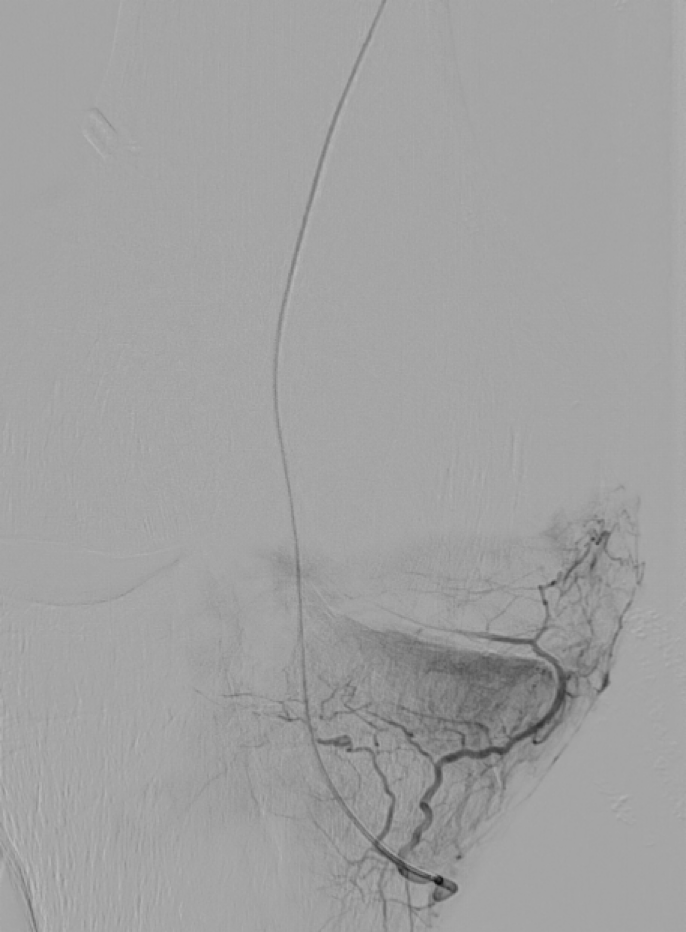

3. Angiographie : Un produit de contraste est injecté pour obtenir des images détaillées des artères du genou et déterminer précisément les zones inflammatoires à emboliser.

4. Embolisation : Une fois que le cathéter est placé correctement, un matériel d'embolisation résorbable (comme un mélange de produit de contraste ou des micro particules) sont injectés pour obstruer les artères ciblées, réduisant ainsi le flux sanguin vers la zone douloureuse.

Artériographie fémorale superficielle Artériographie supra sélective de l'artère géniculée inféro-médiale